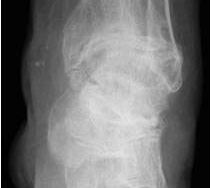

• Primäre oder posttraumatische Arthrose des OSG und USG (Abbildung 1, Abbildung 2).

• Pseudarthrosen (Abbildung 5, Abbildung 6).